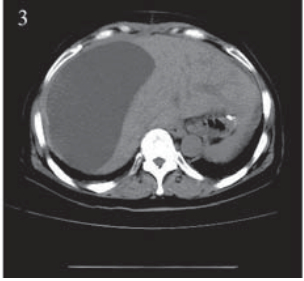

患者,女,66岁。2011年12月因“进食哽噎3 月余”就诊,查胃镜:贲门大弯后壁可见一大小约 3.5 cm×3.9 cm的不规则溃疡,周边堤样隆起。全 身CT等检查提示无其他部位转移,遂于2011年12 月22日在上海中山医院行贲门癌根治术,术中探 查见贲门部病灶,约3 cm×4 cm,质地中等,周围 脏器未见异常,遂行贲门癌根治术,食管胃机械 吻合。术后病理:“贲门”溃疡型腺癌,Ⅱ~Ⅲ级, 侵及胃壁全层及周围脂肪组织,淋巴结(3/20) 见癌转移。TNM分期为:ⅢB期(T4aN2M0), 术后复查CT:两肺少许间质性改变,后腹膜淋巴 结稍大,右肾上极局部形态异常,伴右肾囊肿。 2012年1月27日起予“奥沙利铂+替吉奥”化疗六周 期,期间复查CT无转移依据。2012年8月再次复 查CT:左肺叶间胸膜增厚,右肺上叶可疑小结 节,胃癌术后改变,肝脏小囊肿可能,肝右叶包 膜下包裹性积液,右肾上极梗死后遗改变可能, 右肾小囊肿、小结石,腹盆腔积液,见图 1。查 CA199:154.71 IU/ml,CEA:15.65 ng/ml,肿瘤 进展,遂予“紫杉醇+替吉奥”化疗一周期。2012 年11月初患者出现右上腹胀痛,进食后明显,伴 恶心、呕吐,呕吐物为胃内容物。遂入住我科。 入院查体:右上腹可触及包块,有压痛,中上腹 部可见陈旧性手术疤痕,肝区叩痛明显,余未 见异常。血常规、肝肾功能正常。CA199:143.3 IU/ml,CEA:16.56 ng/ml。腹腔B型超声:腹腔 积液,最大前后径约26 mm;肝包膜下巨大囊性 占位,大小约16.3 cm×9.5 cm,见图 2 。胸部CT未 见异常。腹盆部CT:胃癌术后改变,肝脏小囊肿 可能,肝右叶包膜下包裹性积液较前明显增加, 右肾上极梗死后遗改变可能,右肾小囊肿、小结 石,右肾轻度积水,腹盆腔积液,见图 3。

图 3 肝包膜下巨大囊性转移瘤患者腹部CT Figure 3 Abdominal CT of huge cystic metastatic tumor of hepatic subcapsular The encapsulated fluid undethe right lobe of the liver capsule was increased significantly |